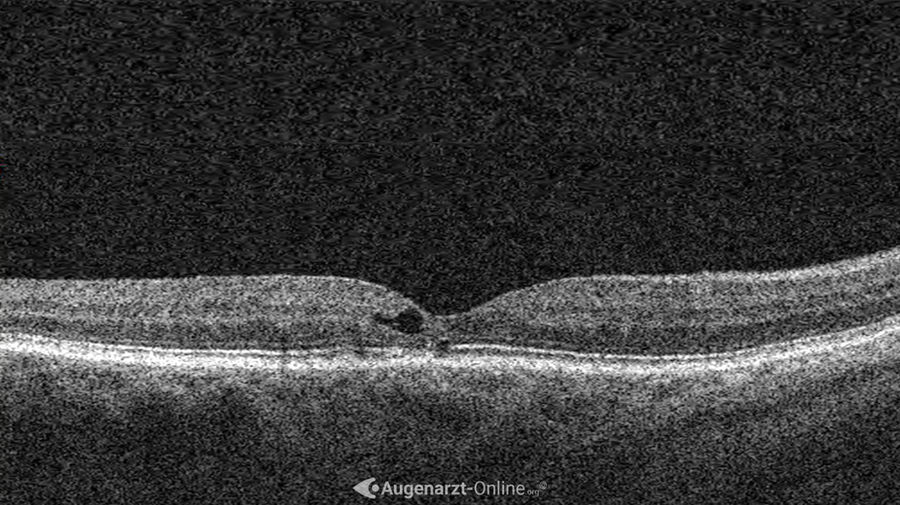

Optische Kohärenztomographie (OCT)

Im horizontalen Schnitt zeigen sich makuläre Teleangiektasien als hyporeflektierende Hohlräume. Diese befinden sich im Inneren der Netzhaut und sind oft von einem leicht hyperreflektierenden Rand umgeben. Oftmals kommt es zu Disruptionen der darunterliegenden Photorezeptoren.